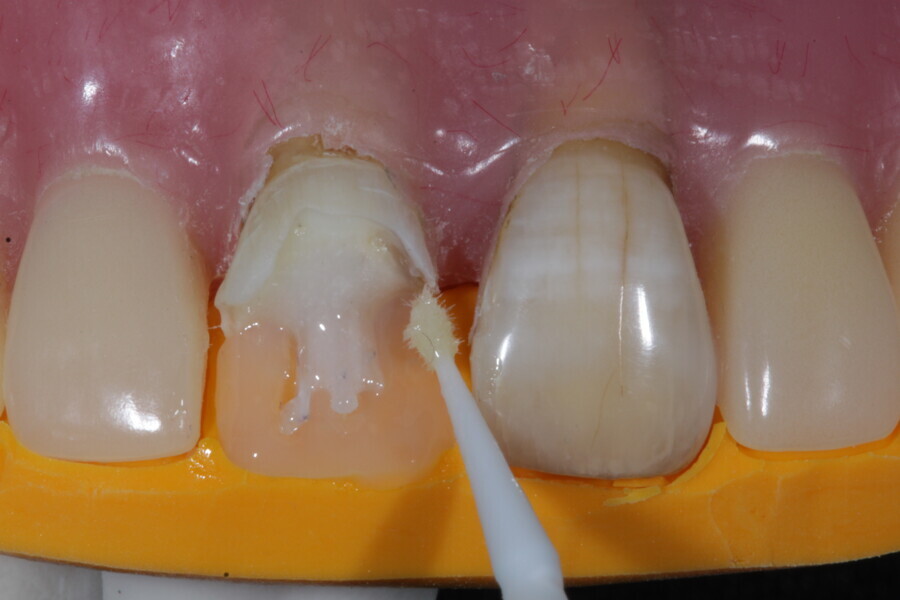

The second step focuses on reinforcing the restoration through careful fibre and FRC selection and placement. Tooth preparation should involve minimal removal of tooth structure to preserve as much natural tooth as possible in preparing the cavity for the restoration. Fibres or layers of FRC (flowable, paste, cube, etc.) are then strategically placed within the prepared tooth and composite material to reinforce areas susceptible to high stress and occlusal forces based on occlusal contact mapping. This strategic selection and placement of fibres and layers of FRC is crucial for enhancing the strength and longevity of the restoration.

Restore

The third step is to restore the tooth to its natural form, function and aesthetics. Composite resin, along with fibres or fibre-reinforced flowable or fibre-reinforced dentine substitute materials, is carefully applied to the prepared tooth structure. A layering technique is often used to ensure proper adhesion and integration of the reinforced materials with the composite material, enhancing the overall strength and functionality of the restoration. The composite resin is then polymerised using a curing light, ensuring that the materials are securely bonded within the restoration and providing a stable and long-lasting result. During this restorative process, the clinician should take special care not to expose fibres or FRC layers to the oral environment, as this can cause tissue irritation and water absorption by the materials in the long run. Therefore, the final layers of the restoration should always be a suitable aesthetic conventional composite resin.